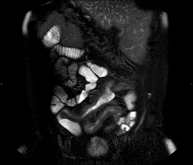

Prueba diagnóstica no invasiva que consiste en el estudio de las arterias renales, obteniendo imágenes de alta definición anatómica mediante el empleo de un campo electromagnético y ondas de radio (con un emisor y un receptor). Es indispensable el uso de contraste paramagnético (Gadolinio). Sin embargo, no utiliza radiación ionizante. La calidad de las imágenes permite realizar reconstrucciones en 2D y 3D. Esta prueba está indicada por ejemplo en aquellos pacientes que sufren de HTA refractaria al tratamiento, en pacientes con lesiones renales para tener un mapa "vascular" pre-quirúrgico, etc. - Entero-RM

Prueba diagnóstica no invasiva que consiste en la obtención de imágenes de alta definición anatómica del intestino mediante el empleo de un campo electromagnético y ondas de radio (con un emisor y un receptor). No utiliza radiación ionizante. Normalmente requiere el empleo de contraste paramagnético (Gadolinio). Está indicada principalmente en el diagnóstico, seguimiento y control de respuesta al tratamiento de los pacientes con Enfermedad de Crohn. - RM Rectal